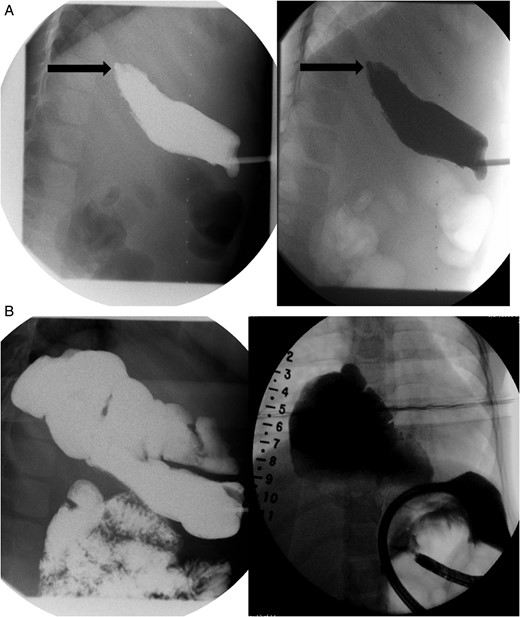

Daily tightening of her traction sutures was performed until the distal esophageal segment reached the chest wall (Fig. 2). The cervical esophagostomy was also sequentially lengthened and eventually internalized. Three traction suture revisions and two proximal esophageal lengthening operations were performed before esophageal continuity was re-established (46 days). Two subsequent anastomotic leaks occurred; 1 anastomotic leak was repaired surgically, whereas one subsequent leak was managed nonoperatively with a chest tube. Five dilations and, one, 13-day retrievable stent placement were needed for anastomotic narrowing. A comparative postoperative esophagram and intraoperative esophagram illustrated neither a stricture nor an anastomotic leak (Fig. 3). Total hospitalization was 112 days.

Fluoroscopic examination illustrating incremental ‘growth’ of the distal (lower) esophageal segment while the patient was undergoing external traction (Foker Stage 1). The contrast was injected through her existing gastrostomy tube. The metal dot refers to her esophagostomy; thus, can measure the distance between the ends of her esophageal segments.